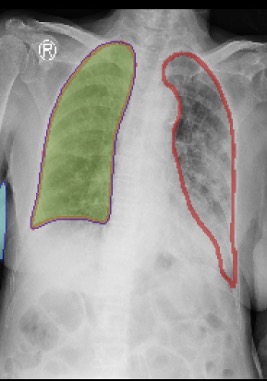

Figure 3: Sample outputs from various datasets showing regions of interest generated from SAM2.

Figure 3 shows the regions of interest generated by SAM2 for various datasets.